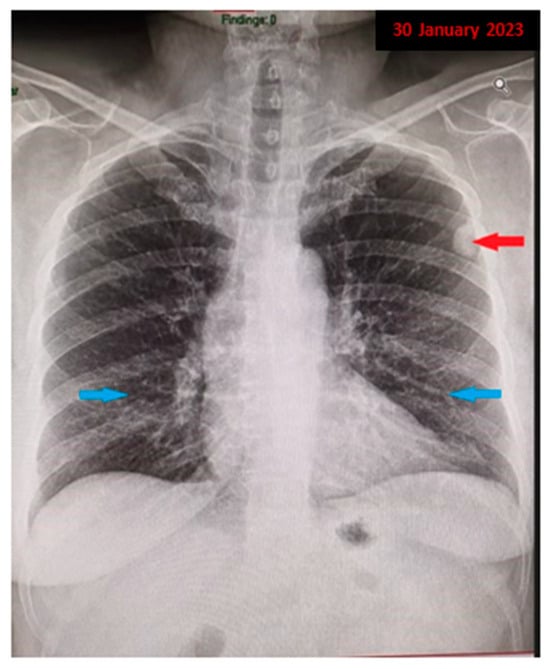

Figure 2. A chest CT was performed, which revealed subpleural micronodular and nodular pulmonary lesions located in the upper lobes bilaterally, up to 13/22 mm ((a): red arrow), associating thickening of the interstitial septa, acquiring a right subpleural pseudo-nodular appearance ((b): red arrow). Additionally, mediastinal lymphadenopathy was observed in Barety’s space, measuring approximately 10 mm ((c): red arrow), and pulmonary interstitial involvement with a ground-glass appearance in the lower lobes ((d): red arrow). The nonspecific clinical context, associated with the presence of observed imaging changes, prompted further investigations, raising suspicion of diffuse interstitial lung disease. Meanwhile, the patient’s pulmonary function tests indicated normal values, but with a slight decrease in the diffusing capacity of the lung for carbon monoxide (DLCO), with an estimated DLCO value of 72% of the predicted values. Additionally, the patient underwent a fiberoptic bronchoscopy examination, revealing bilateral bronchial secretions, otherwise normal laryngeal dynamics, and no apparent proliferative elements or active lesions of the mucosal tissue in the examined areas. The microlavage of the left upper lobe bronchus was evaluated for bacteriological exams and did not yield any pathogenic micro-organisms. Ziehl–Neelsen staining from the lavage liquid also revealed no acid-fast bacilli. Despite the extensive and thorough investigations conducted previously, the etiology of the polymorphic pulmonary lesions could not be established.